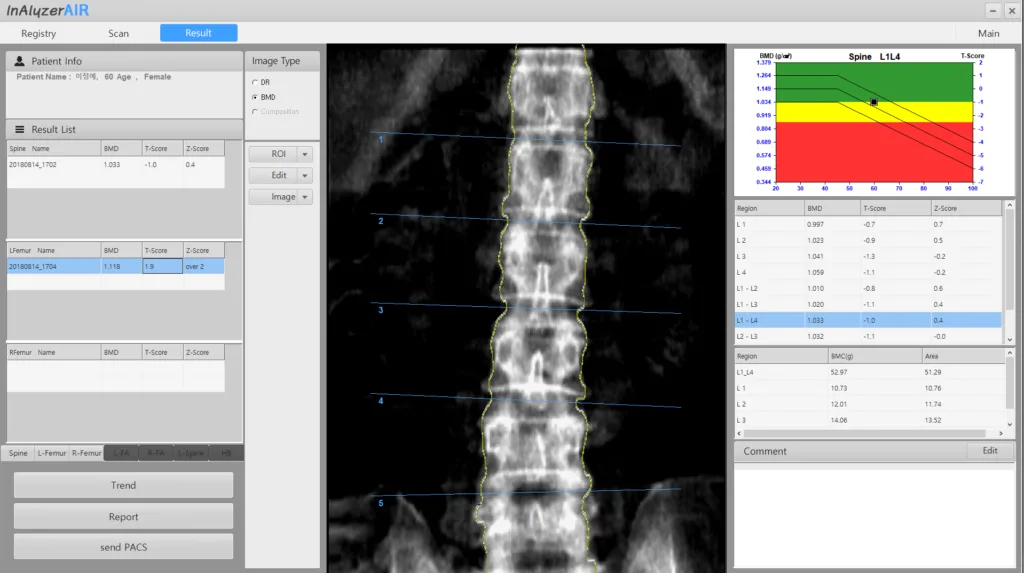

Powerful Software

Es bietet verschiedene Diagnosetools und ermöglicht bequeme und genaue Messungen durch intuitive Software. Darüber hinaus können Sie durch die Aufrechterhaltung der Leistung der Geräte durch Wartung stets zuverlässige Ergebnisse erzielen.